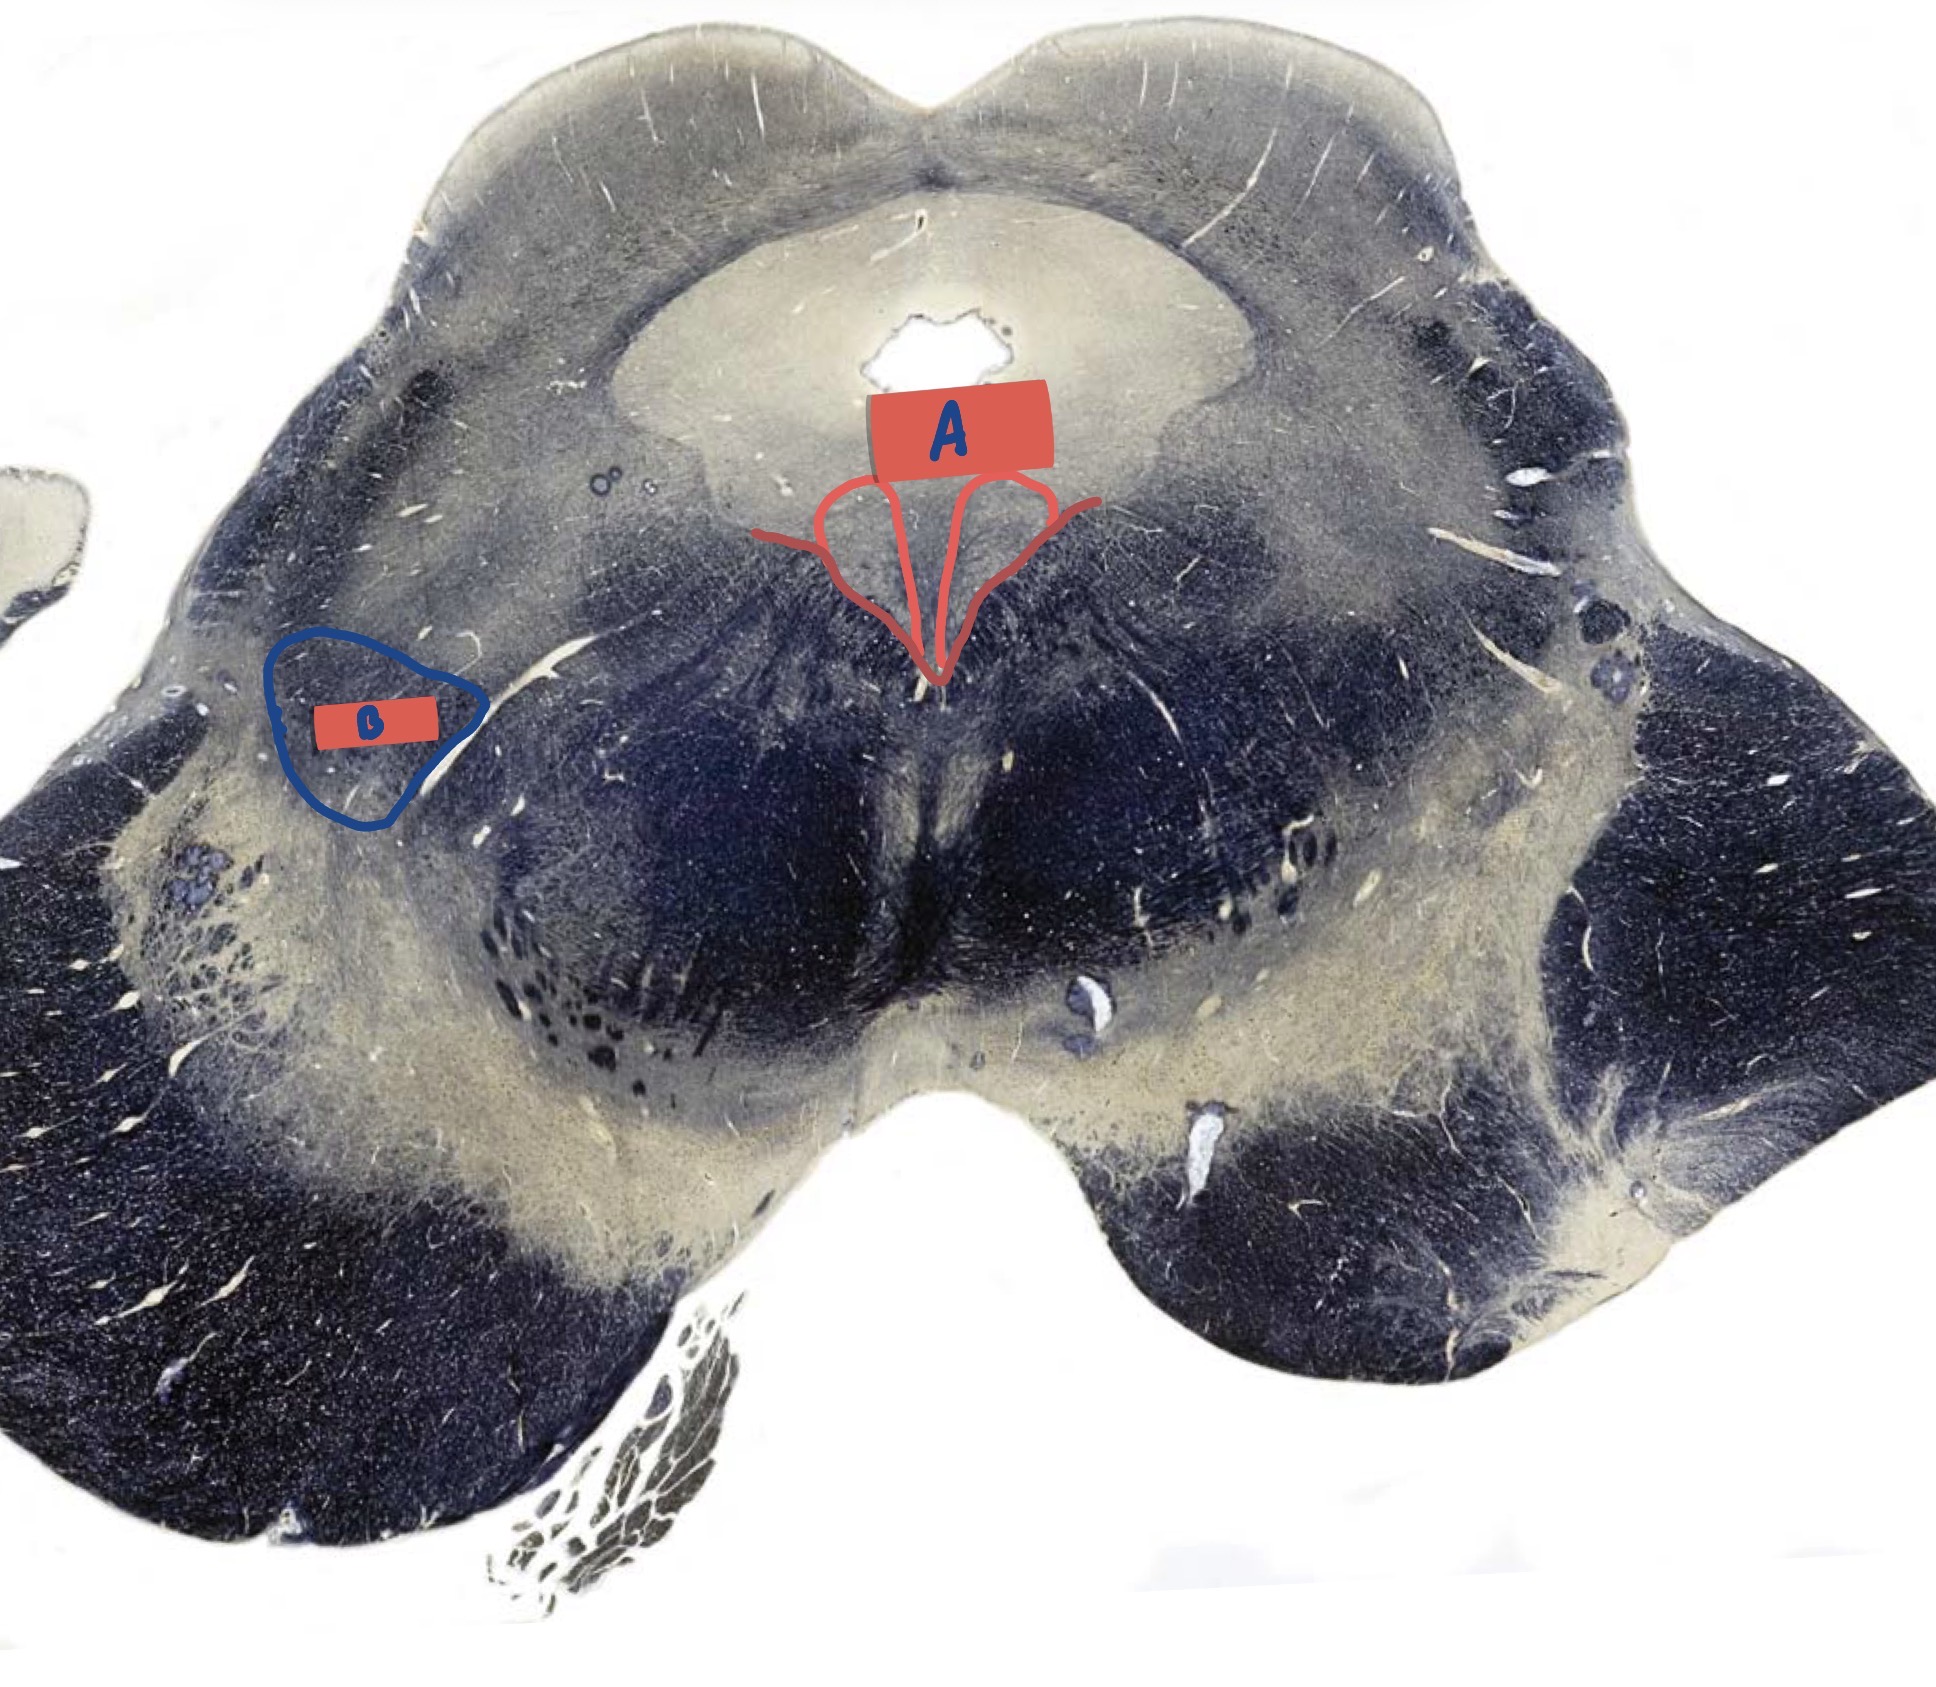

What is A?

Sulcus limitan

What is B?

Hypoglossal nucleus

What is C?

Dorsal motor nerve of Vagus

What is D?

Medial vestibular nucleus

What is E?

Solitary nucleus

What is F?

Medial longitudinal fasciculus

What is G?

Nucleus ambiguus

What is H?

Medial lemniscus